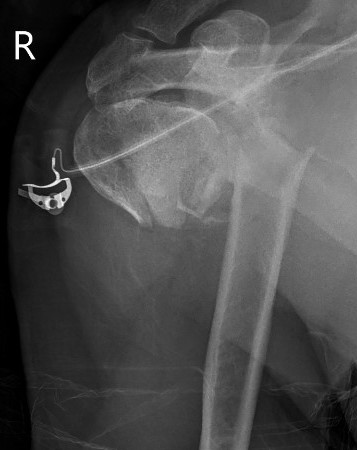

Hemiarthroplasty

Indications

Unreconstructable fracture - 4 part, comminuted, head spltting fracture

Insufficient glenoid

Patients too young for rTSA

Complications

Loss of tuberosity fixation